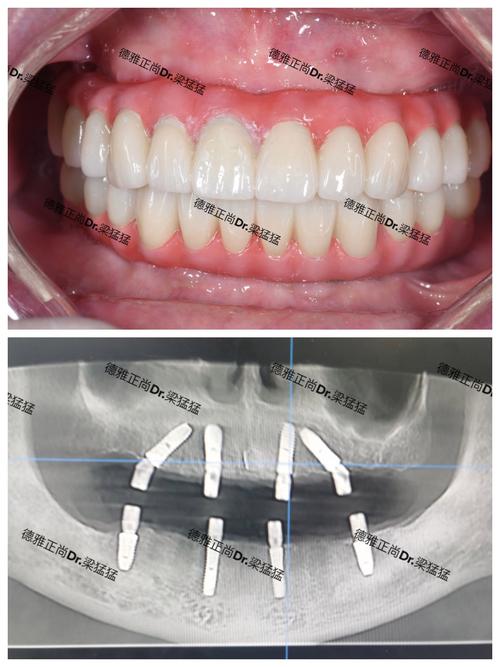

(图片来源网络,侵删)- 局部麻醉下,切开牙龈,暴露牙槽骨。

- 在预定位置、角度、深度精确植入3颗种植体。

- 根据情况决定是否同期植入愈合基台或覆盖螺丝。

- 缝合牙龈。